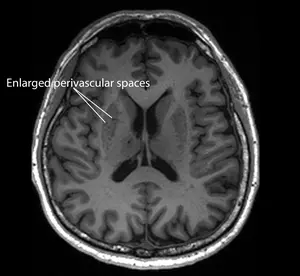

This suggests that such clogged drains, a condition known as “enlarged perivascular spaces”, are a likely early-warning sign for Alzheimer’s, a common form of dementia.

“Since these brain anomalies can be visually identified on routine magnetic resonance imaging (MRI) scans performed to evaluate cognitive decline, identifying them could complement existing methods to detect Alzheimer’s earlier, without having to do and pay for additional tests,” said Associate Professor Nagaendran Kandiah from NTU’s Lee Kong Chian School of Medicine (LKCMedicine) who led the study.

If these drains get clogged because the brain’s system of clearing toxic waste is not working efficiently, they form enlarged perivascular spaces, which can be seen on MRI scans. But it was not previously clear if this condition was also linked to dementia, specifically Alzheimer’s disease.

For the latest study, the researchers analysed the MRI scans of the participants and found that those with mild cognitive impairment tend to have clogged drains in their brains, or enlarged perivascular spaces, compared to the other participants.

“The findings carry substantial clinical implications,” said Assoc Prof Kandiah. “Although white matter damage is more widely used in clinical practice to evaluate for dementia, as it is easily recognised on MRI scans, our results suggest that enlarged perivascular spaces may hold unique value in detecting early signs of Alzheimer’s disease.”